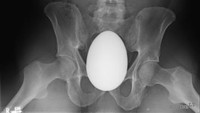

Seorang pria 41 tahun di Amerika Serikat dibawa ke unit gawat darurat dengan keluhan nyeri panggul hebat, akibat benda besar berbentuk oval dimasukkan 2 jam sebelum pasien datang. Setelah dicek dokter, itu adalah kelereng berbentuk telur. (Foto: International Journal of Surgery Case Reports)